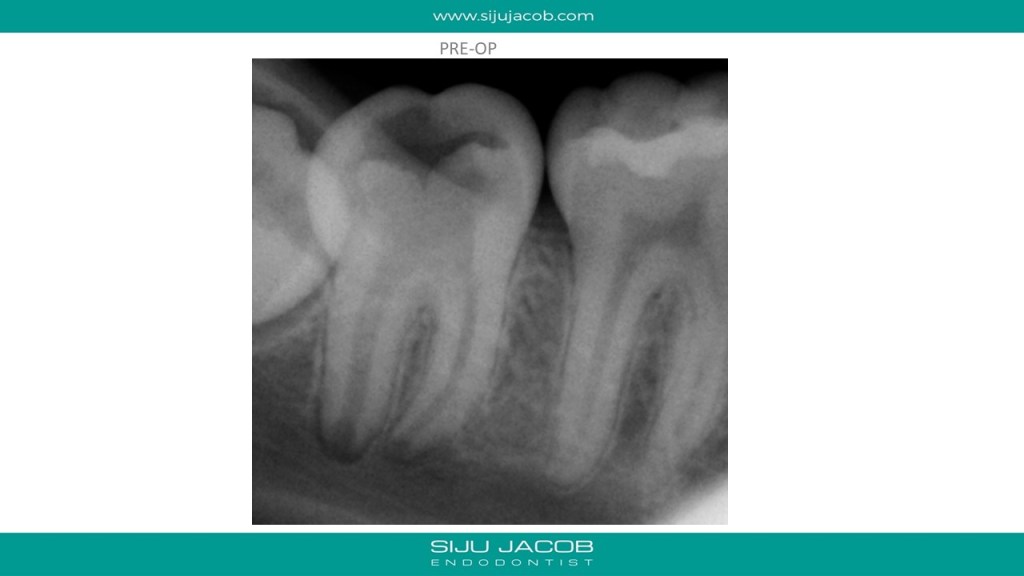

This young patient first came to me with a pulpal exposure in a grossly decayed mandibular second molar. The root formation wasn’t completed and restorative prognosis too wasn’t great. The pulp in the chamber was very inflamed. So, I cleaned up the pulp in the chamber and left the pulp in the canals as it is. I filled the pulp chamber with MTA and closed the cavity with Glass Ionomer. I thought I’d recall and evaluate. The patient was supposed to come back after 3 months. Instead, he came back after 3 years with the Glass Ionomer restoration dislodged. The root formation looked complete in both roots. The tooth was pitch-black from the MTA. After cleaning up everything, I found that the mesial-canals were exposed, but the distal canal was blocked with a solid coronal barrier. I didn’t see any reason to drill through the dentine in the distal root. I decided to obturate only the mesials and left the distal alone. I advised extraction of the third molar and an Onlay. It would be interesting to see how this turns out.